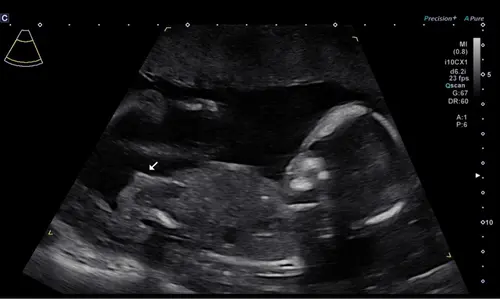

Lastig te zien op deze foto!

Ja daar was ik al bang voor helaas :(

Ook niet goed te zien helaas.. zie je niet rechts bij de beentjes op een andere foto een betere met een witte streep?